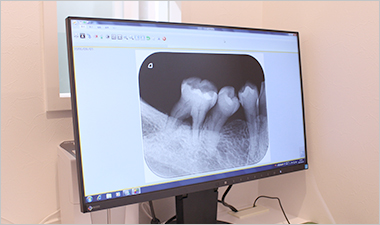

ビスタスキャン

それぞれの歯ごとに画像化するときに使用します。

デンタル撮影にはビスタスキャンを採用し、口腔内に入れるイメージングプレートは最小限のサイズで最大限の画質を得ることができます。